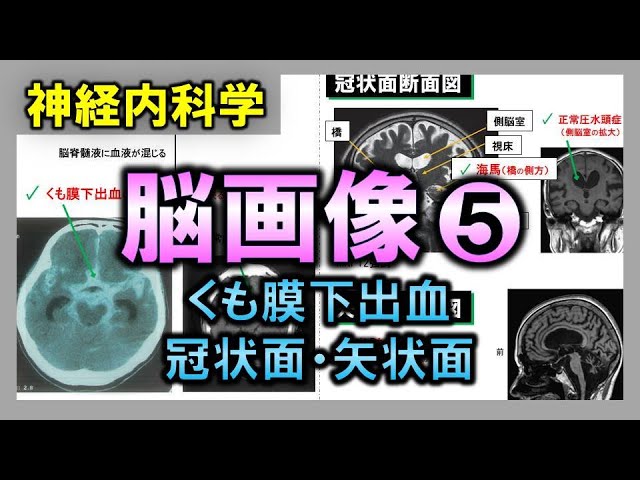

冠状面 (364 無料画像)

弁護士 小松亀一法律事務所_交通事故_MRI・CT写真の切り口用語解説。